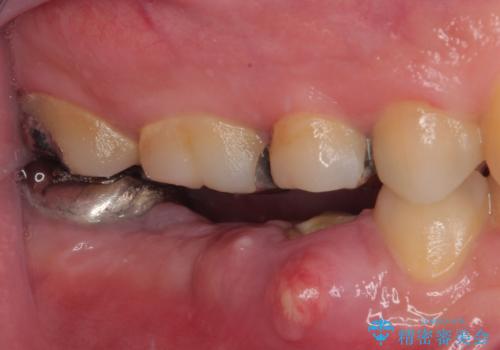

抜歯即時埋入部と後方の欠損部は、即日荷重(インプラント埋入と同時に仮歯を装着すること)が可能な安定値が得られましたが、長い期間欠損した状態で過ごすと、欠損部に舌を押し当てる癖が発現してしまい、舌からの側方圧でインプラントが脱離するリスクが著しく高まってしまうため、即日荷重は行いませんでした。

おかげでインプラントは無事に生着し、僅か4ヶ月で治療を終えることができました。